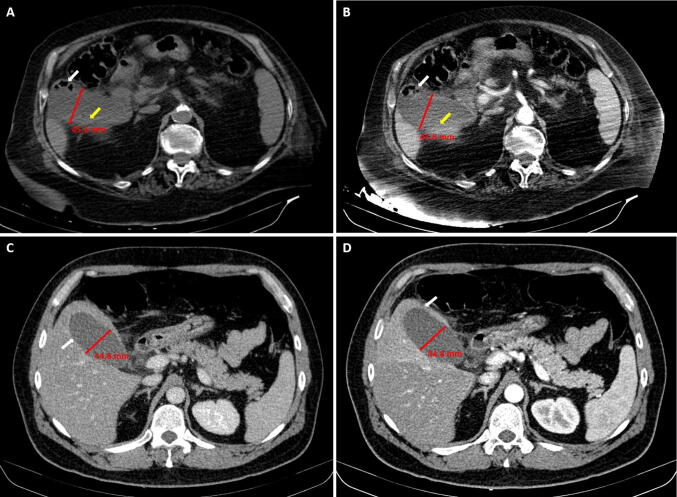

Fig. 1.

Contrast-enhanced CT scans showing markedly distended and thickened gallbladder with reduced wall enhancement. a, b Without (a) and with (b) contrast enhancement (arterial phase). White arrow indicates gas in the gallbladder wall. Yellow arrow indicates intraluminal linear densities. c, d Without (c) and with (d) contrast enhancement (arterial phase). White arrow indicates the absence of gallbladder wall enhancement (c) and perforation of the fundus (d)

We wish to highlight and discuss a rather different clinical scenario, that is the case of surgical emergencies that occur during hospitalization for established SARS-CoV-2 infection in patients who are recovering from pneumonia. As of February 2020, Italy became the second epicenter of Covid-19 in the world. Most general hospitals in Lombardy and Milan area, including our 450-bed University Hospital, were converted to Covid facilities to provide intensive-care resources for this patient population. Over the past 2 months, we managed three patients, one female and two males aged 86, 72, and 40 years, respectively, who developed acute abdomen while recovering from Covid-19 pneumonia. Contrast-enhanced abdominal CT scan revealed markedly distended gallbladder and decreased wall enhancement consistent with acute acalcolous cholecystitis (Fig. 1). Emergency laparoscopy confirmed gallbladder gangrene in all, associated with fundic microperforation in the youngest patient, and cholecystectomy was completed without complications and no conversion. To prevent aerosolization, the pneumoperitoneum was set at 9 mmHg, use of electrocautery was minimized, and smoke was safely aspirated through a filtered smoke evacuation system.